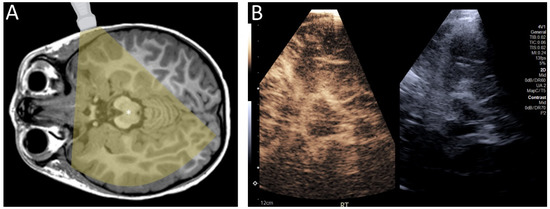

While most of these studies have focused on CEUS in infants, which are an obvious target population for CEUS because of their fontanelles, CEUS may be used in older children and adults through a transtemporal window (Figure 4). The squamous part of the temporal bone is thin and often allows for the sufficient penetration of sound energy to permit ultrasound imaging. Although attenuation by bone can partially limit visualization of intracranial structures, the use of contrast allows visualization of intracranial microvessels as compared to transcranial Doppler, which is limited to macrovascular imaging [23,24]. This has several theoretical uses, including evaluation of stroke [25,26,27,28,29], more subtle perfusion changes in the setting of arterial stenosis [30], and brain death [24]. Other windows, such as transcondylar, suboccipital, and transforaminal through the foramen magnum may increase the probability of intracranial macro- and microvascular flow assessment in cases where the transtemporal approach is insufficient.

Figure 4.

(A) Diagram demonstrating the transtemporal approach for ultrasound. (B) Contrast-enhanced ultrasound of the brain of a 4 year old child through a transtemporal window. In infants, ultrasound can be performed through open fontanelles. In older individuals, including children and adults, ultrasound can be performed through the transtemporal window.